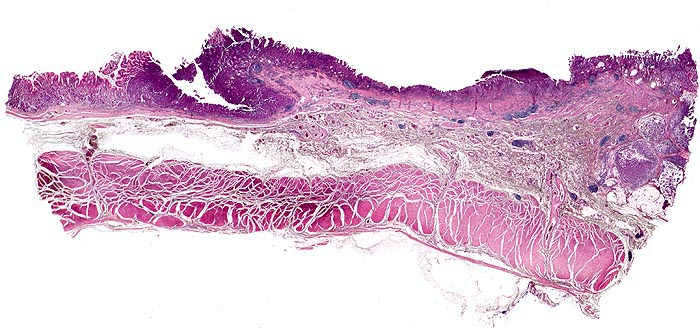

Am unteren Ende des Präparates Antrummukosa mit mässiggradiger chronischer, geringgradig aktiver Gastritis und ausgedehnter intestinaler Metaplasie (Becherzellen).

Weiter oben Invasion der Magenschleimhaut durch ein teils solides, teils drüsenbildendes Adenokarzinom mit stark atypischen Tumorzellen.

Fokale Erosion des Karzinoms bedeckt von fibrinoleukozytärer Membran.

Tumorinfiltration der Submukosa an der oberen Präparathälfte.

Der invasive Karzinomanteil zeigt teilweise muzinöse Differenzierung (teils siegelringzellige Tumorzellen schwimmen in extrazellulären Schleimseen).

Tumorfreie Lamina muscularis propria.